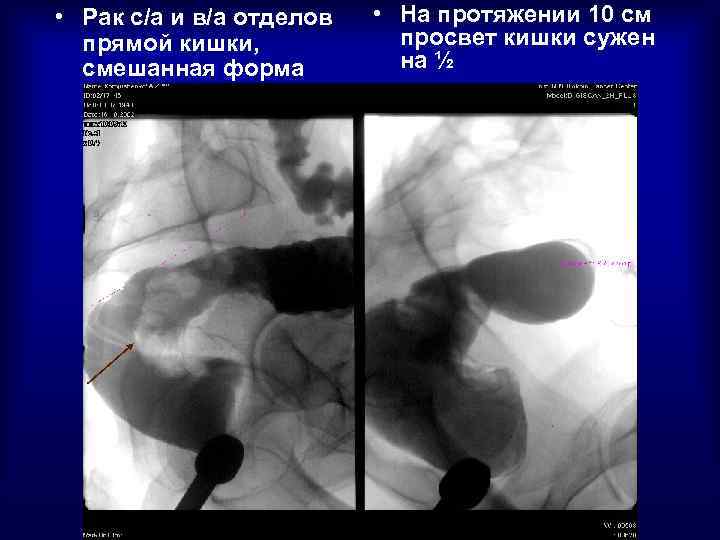

Рак прямой кишки

• Рак с/а и в/а отделов прямой кишки, смешанная форма • На протяжении 10 см просвет кишки сужен на ½